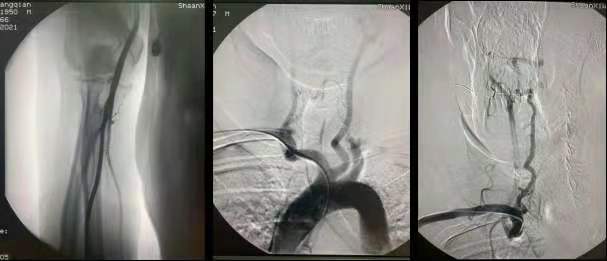

造影:泥鳅导丝辅助下,将Pigtail猪尾巴管送入升主动脉,行主动脉弓造影;完成造影后,导丝把猪尾巴管撑直,然后将泥鳅导丝和猪尾巴管一同退出体外;也可以沿猪尾巴管放入0.35in 260cm交换导丝,保留导丝交换出猪尾巴管,再由SIM2管沿交换导丝放入主动脉弓;依次行双侧颈动脉、锁骨下动脉、椎动脉造影。

全脑血管造影术(digital subtraction angiography,DSA)是诊断脑血管疾病如颅内外血管狭窄、动脉瘤、动静脉畸形、烟雾病等的金标准,并为进一步治疗提供重要的资料信息。长期以来,股动脉入路脑血管造影因股动脉粗直,容易定位,穿刺成功率高,易于介入手术操作,为神经介入医师广泛采用,已成为脑血管造影术的经典路径。但是,股动脉穿刺存在诸多不足,如因股动脉解剖位置较深,术后止血困难,易导致局部大出血、皮下血肿、假性动脉瘤等;局部压迫力度过大可发生迷走神经反射导致心率减慢、低血压等并发症。术后需严格卧床24h,易出现腰痛和排尿困难,并易发肺部感染、下肢静脉血栓形成等不良事件。